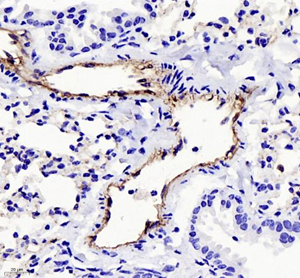

| Immunohistochemistry of paraffin embedded mouse ovary using CD31 (GB11063-3) at dilution of 1:400 (400x lens) |